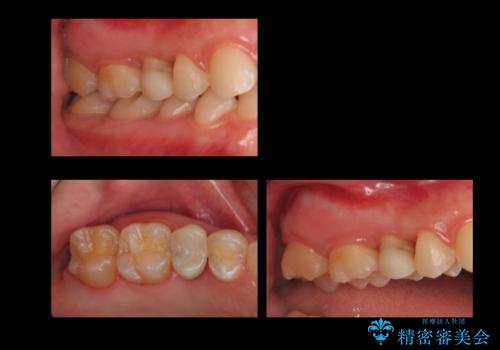

歯周外科治療で歯の高さを出し、外れにくくしました。

セラミックにする前後でマウスピース矯正治療を行なっています。(以下のリンク参照)

- 21万円(右上4:ジルコニアクラウン10万円、仮歯 1万円、歯周外科治療(APF) 10万円、矯正用仮歯 2万円費用は治療当時の料金となります